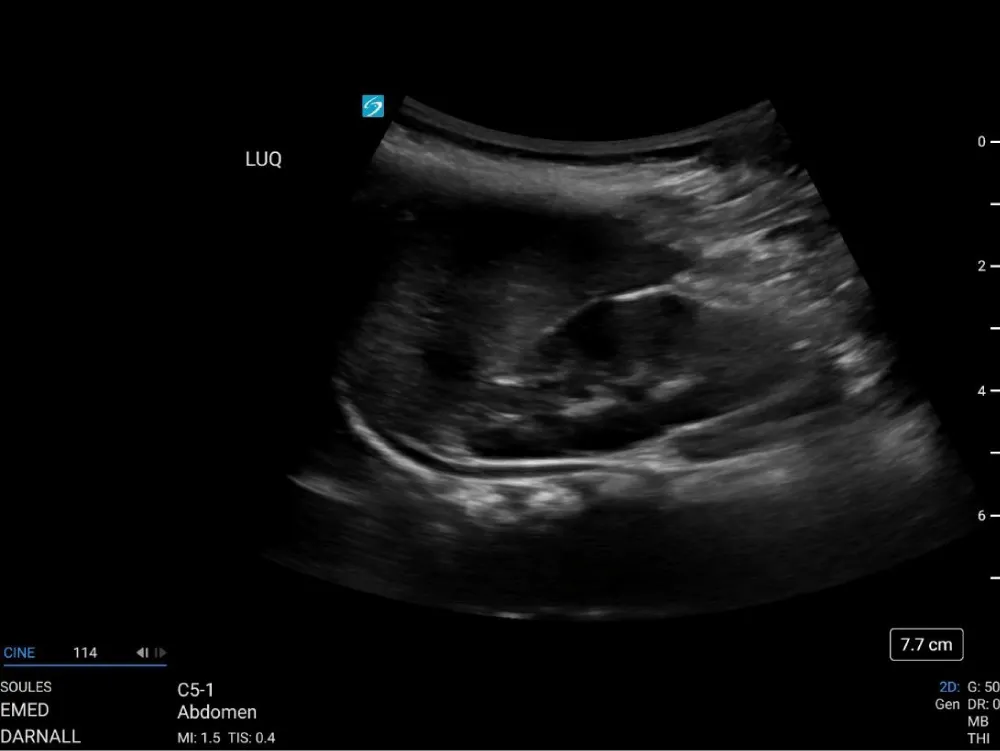

Hypothesizing that the anechoic stripe in the left upper quadrant might be an artifact resulting from image processing, as suggested by Baer Ellington, et al. [17] the point of care FAST exam was repeated by the ultrasound faculty member, an individual with more than a decade of experience, well over a thousand scans, and multiple sonography certifications, using a GE Venue ultrasound system (General Electric, Boston, MA) with a 1-5 MHz curvilinear probe and abdominal settings. The left upper quadrant window was again concerning for a subdiaphragmatic anechoic stripe (Figure 2 and Video 2).

Video 2: Cine loop of the repeat LUQ FAST examination obtained using the GE Venue ultrasound system.